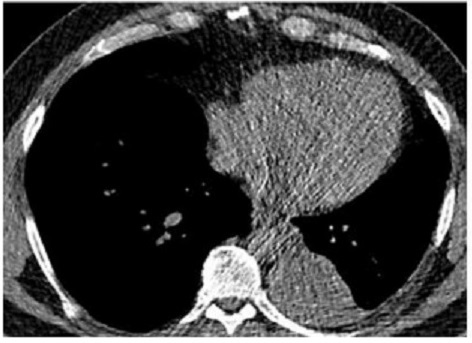

Aspect radiologique TDM

de masse isodensite paravertébrale gauche hétérogène

volumineuse, contenant des zones de densité négative,

graisseuse . Image radiologique TDM du thorax sans

contrast intraveineuse coupe axiale |